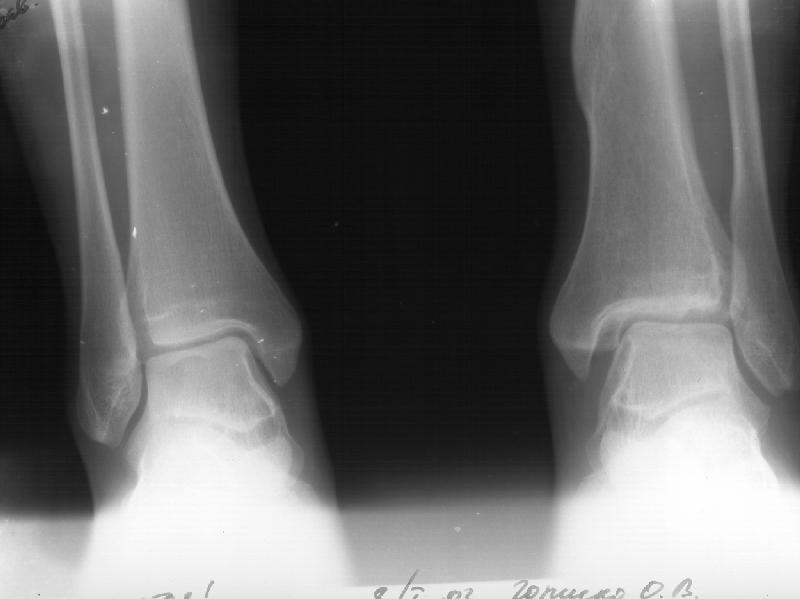

На следующий день пациентке сделали КТ. Может быть, после просмотра картинки будут другие предложения? Не убрать ли ве-таки этот фрагмент

позади внутренней лодыжки, который оттесняет таран кнаружи?

Думаю, КТ прочитан не верно. Задняя часть медиального маллеола, в сущности уже часть заднего маллеола стоит на месте и трогать её не следует. Передняя часть маллеола на 3-4 мм удалена от тарана. Сравните с пространством между

латеральным маллеолом и тараном. В норме все три должны быть одинаковы: между тараном и латеральным, задним и медиальным. Это главное условие устойчивого сидения тарана в голеностопном суставе.

Все-таки она как раз была была отколота и вместе с тараном смещена латерально.

> Передняя часть маллеола на 3-4 мм удалена от тарана.

Внутренняя лодыжка не была сломана, она как была на своем месте, так там и находится. Это таран от нее отдавлен кнаружи смщенным в его сторону фрагментом позади внутренней лодыжки. За счет чего и есть проявления нестабильности связок.

Вот и проблема. Восстанавливать ли эту равномерность сейчас, и если да, то как. Вот точка зрения коллеги из Штатов: